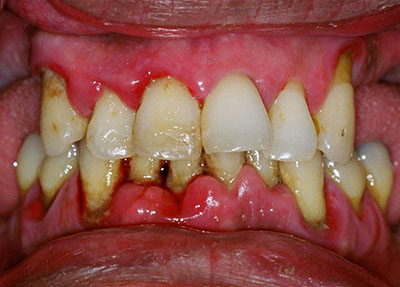

Диагностические мероприятия начинают с выяснения состояния зубов и дёсен, наличия аномалий, изменения цвета тканей, окружающих зубы.

Сначала прощупывают подчелюстные лимфоузлы, при наличии патологии они болезненные и увеличенные. Осматривают ротовую полость на наличие признаков заболевания:

- отёка и красноты дёсен;

- рыхлых краёв десны;

- карманов между десной и зубом;

- большого количества зубных отложений;

- расхождения между резцами;

- подвижности и открытых корней.